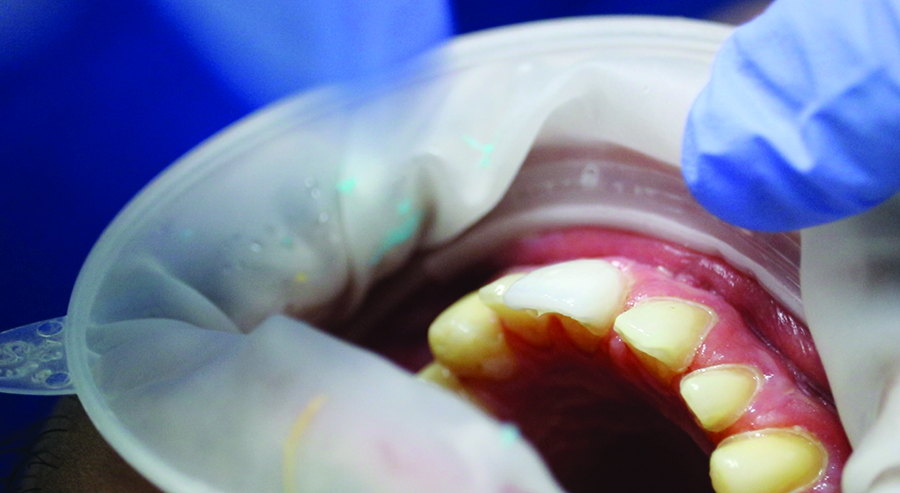

The preparation

Fig. 10B

Occlusal view of the maxilla after preparation.

Fig. 10C

Occlusal view of the mandible after preparation.

A week later, the young man had only minor requests for adjustments to the tooth shape, particularly in terms of length, and he wanted a small reduction in the anterior region, based on the advice of his wife. This was immediately adjusted on the mock-up and approved by the patient. After preparing the teeth they were scanned with Primescan and the data was sent through the Connect Case Center to the laboratory. Because completion of the case was planned for the same day, an additional impression was also taken in the patient’s mouth in order to make an analogous plaster model for the individualization of the cosmetic restorations in the laboratory.

Intraoral scan (Primescan) of the prepared situation.

Fig. 11B

The intraoral scan (Primescan) is sent to the laboratory via CCC